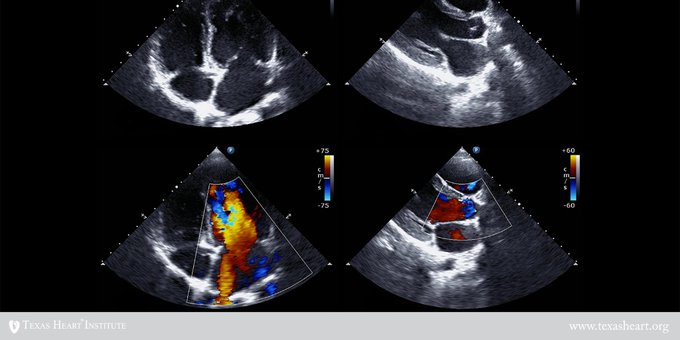

El ultrasonido o ecocardiografía intravascular se realiza junto con un procedimiento llamado "cateterización cardíaca". El ultrasonido intravascular emplea ondas sonoras para producir una imagen de las arterias coronarias Eso y más aquí ow.ly/tVVs50ADFcH